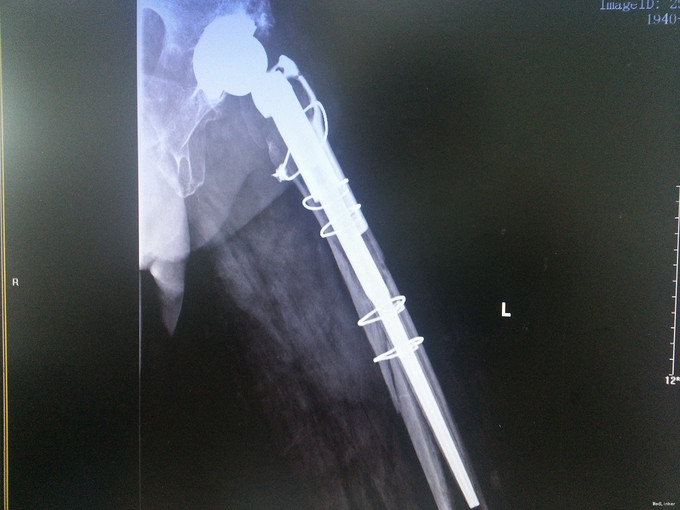

查体:左髋可见一长约8cm的手术疤痕,局部无明显肿胀,左下肢杠力消失,纵向叩击痛(+),肢端血运、感觉及活动良好。 辅助检查:骨盆X片:左股骨假体周围骨折。

诊断:假体周围骨折(左股骨假体柄周围骨折);高血压病;脑梗死后遗症;陈旧性肺结核 治疗:手术治疗[左侧股骨假体取出术+左侧股骨假体周围骨折切开复位钢板钢缆内固定术(zimmer)+左侧股骨假体置入术(MP,Link)] 术中探查及处理:股骨大粗隆崩裂,骨折线自近端向远端延伸至股骨中段,呈螺旋形,骨折块粉碎,移位明显。骨折断端可见淤血块。顺利取出假体柄后,复位骨折块,予复位钳临时固定后,予钢板钢缆(zimmer)加压捆扎。待骨折固定牢靠后,按照髋关节置换流程逐步扩髓,最后选择25omm长的14号假体(MP,Link)安装,36mm标准颈股骨头复位。测试各方向活动良好,松紧度合适。